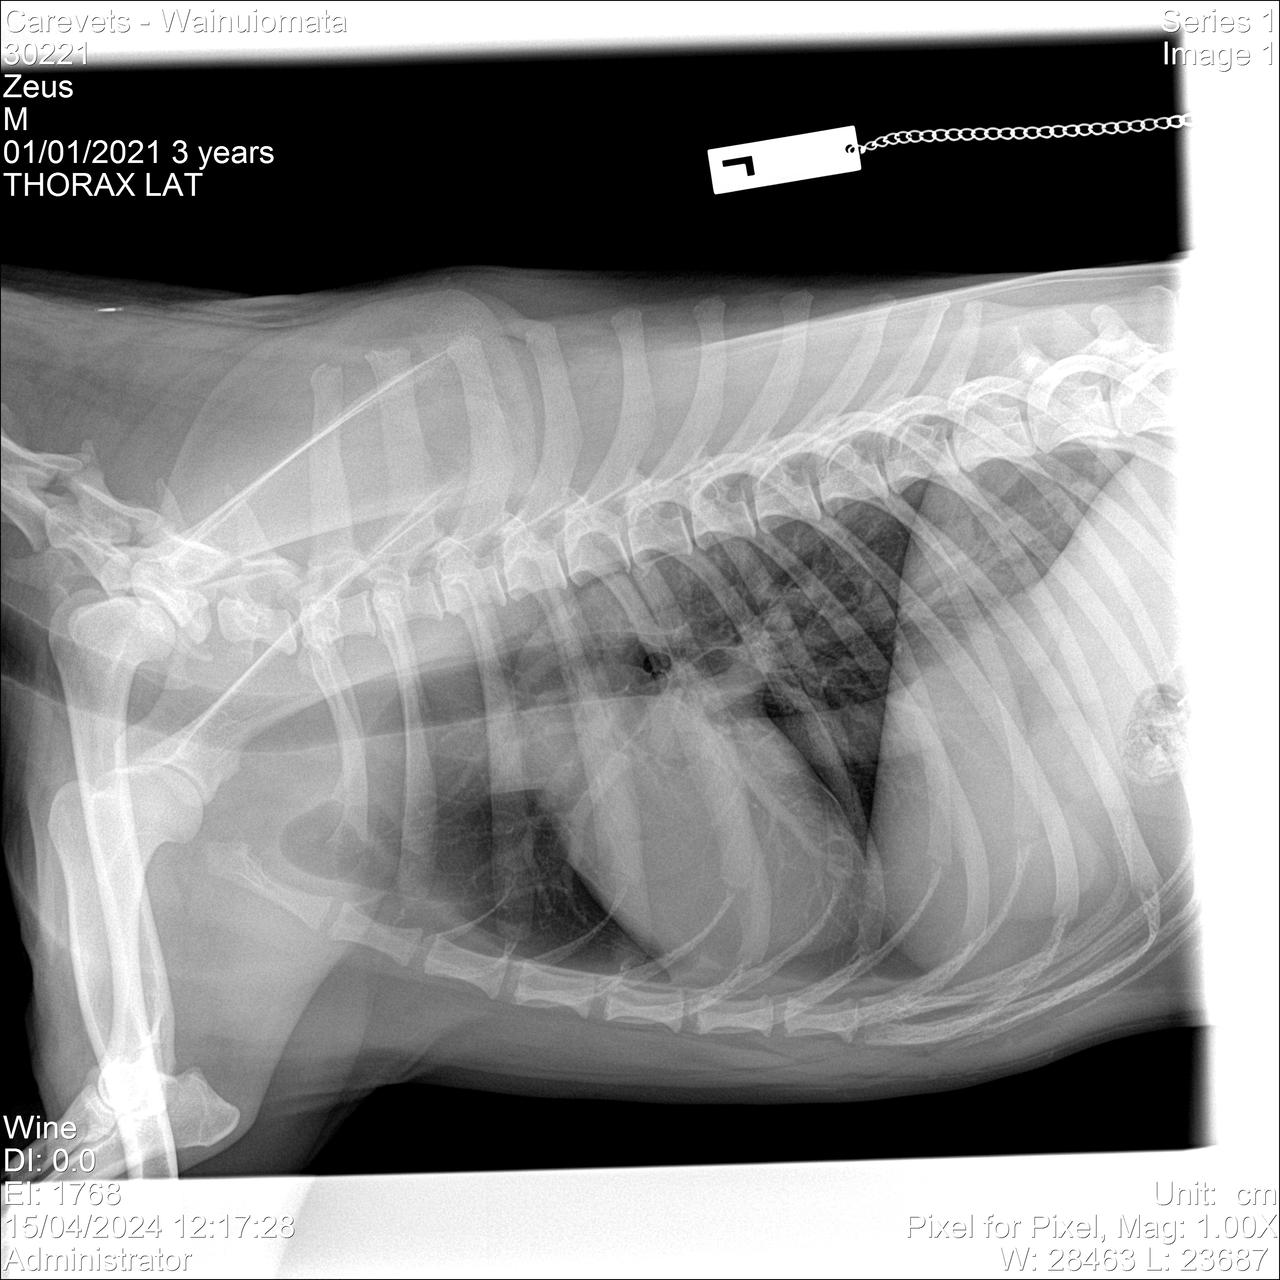

• New Xrays

15 April 2024

Hi All, we took Zeus in today to xray his chest area again and his Amputation is now booked in on the 29/4/24. Thank-you all for the help thus far it's been amazing

• More X-rays and his amputation date

Zeus is going in for another xray in the 15th to compare from his original and to get more views so it can be sent off to a Radiologist to access. His Amputation is booked for the 29th April.

I just hope the Radiologist doesn't find anything and Taking his leg prolongs his life for years to come. Thank you all for the support.

19/03/2024 - $776.40 - Zeus started limping again on the same right hind leg, we took him to the Vet after also discovering a lump on his leg, thinking it was dislocated this time from rough play. They did an x-ray and discovered the Tumor in his Leg, they also xrayed his chest and discovered potential Cancer in his Lungs.